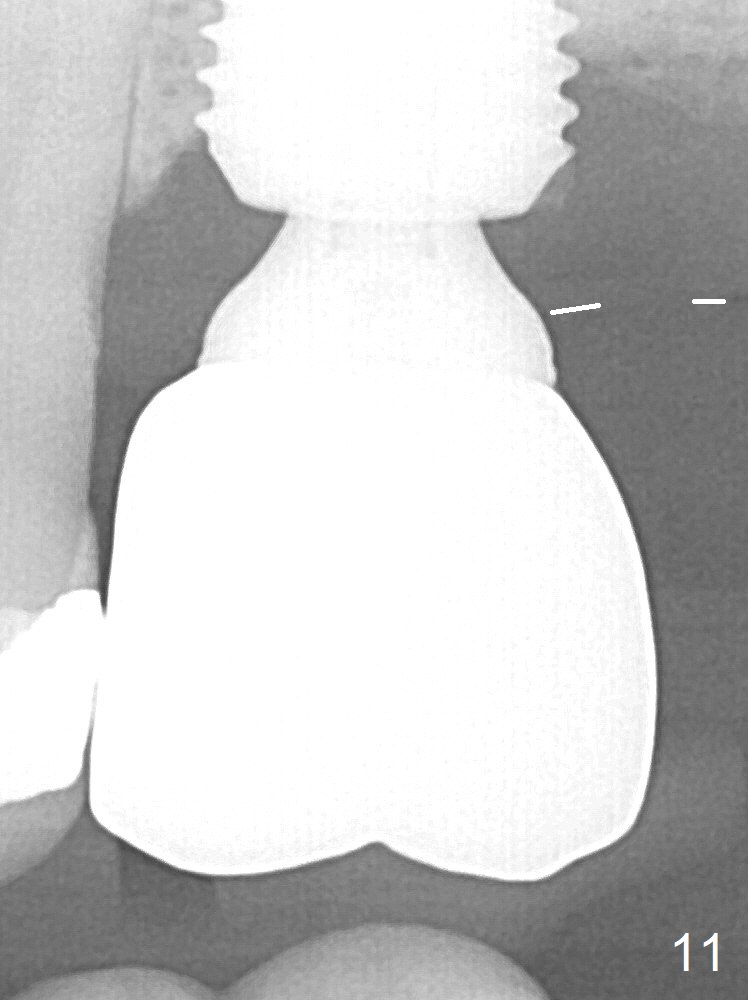

When the patient returns for impression 6.5 months postop, the provisional has dislodged because of the short abutment (Fig.7 A (6.5x4(2) mm). A longer one is placed (6.5x5(3) mm). When he returns for crown cementation 8.5 months postop, the provisional is retentive. The distal implant plateau is still exposed. Post-cementation panoramus shows that the distal 3 threads are not covered by the bone and that the crown/implant ratio is 5:3 (Fig.8). Implants are recommended at #3 and 30 (Fig.9). There is a distinct layer of bone apical to the implant at #14 22 months post cementation (Fig.10 *). In spite of exposure of 2-3 threads distally, there is no sign of peri-implantitis. It appears that the implant is subgingival (Fig.11 (BW) white dashed line: gingival margin). The implant remains infection free 3 years 10 months post cementation (Fig.12) due to the thick gingiva and good oral hygiene.